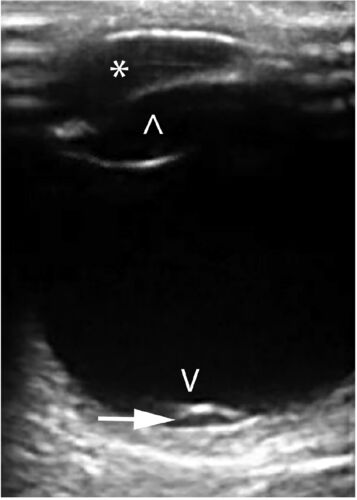

case137:ウエイトリフティング後に霧視と飛蚊症を発症した30歳男性(Ann Emerg Med. 2021 Feb;77(2):269-283.)

症例 ・30歳男性 ・4日前にウエイトリフティングをした際に左目の霧視と飛蚊症を自覚 ・視力…正常/0.5 ・左目の下方の視野欠損を認めた ・ベッドサイドで眼球超音波を実施 ポイントは「息こらえ後に発症した視力障害」です。 診断 Valsalva網膜症 ・1週間後…